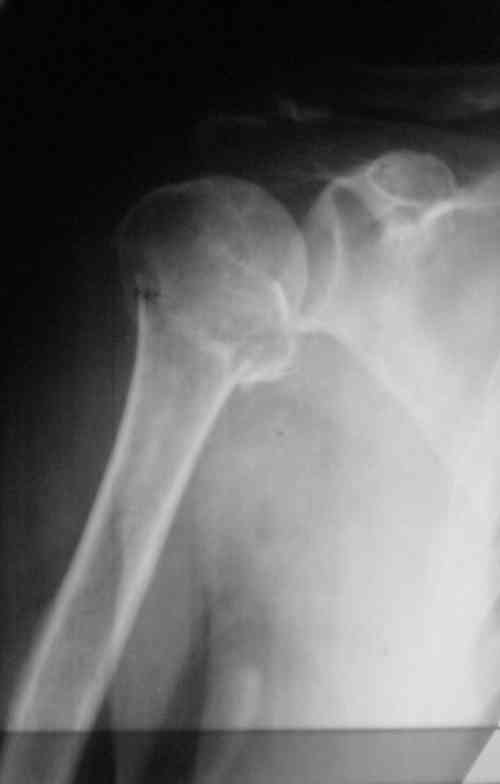

Снимки на 1-е сутки после репозиции и на 8- сутки после репозиции.

Наш недавний случай перкутанной фиксации "методом

Сиэтла" спицами 2.8 мм с резьбой на конце.

Головка плечав небольшом варусе или это проекционное?

На 20-е сутки снял гипс, одел фиксирующюю

ортопедическую повязку. Вот контроль. Как видно, стояние хорошее, уже формируется костный мозоль.

Думаю еще недели 3 продолжать фиксацию.

-Головка плеча в небольшом варусе или это

проекционное?

Да, там имеем небольшой варус, надеемся, что в будущем проблемы не будет.

Из-за большого обьема конечности доступ к бугорку был затруднен, предварительно зафиксированный шуруп не удержал бугорок, поэтому фиксацию провели толстыми нитками. Состоятельность фиксации бугорка обычно проверяем во время операции, под рентген контролем проводится движения конечности, особенно приведение.